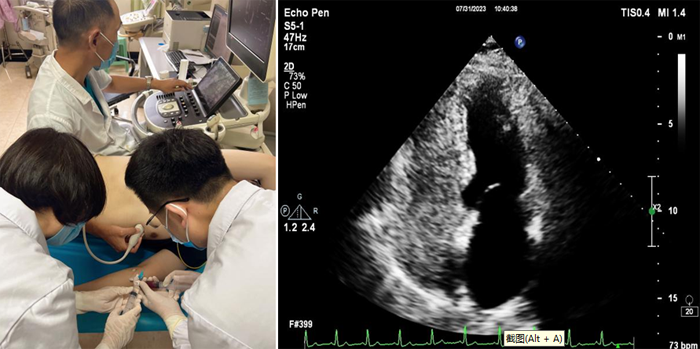

近日,我院超聲科聯(lián)合介入室、CCU 及神經(jīng)內(nèi)科成功完成首例經(jīng)胸右心聲學(xué)造影檢查。該項(xiàng)檢查填補(bǔ)了我院在超聲造影檢查的一項(xiàng)空白,該技術(shù)在魯西南地區(qū)屬領(lǐng)先水平,為我院心腦血管疾病的診斷又添新技術(shù)。

右心聲學(xué)造影又稱發(fā)泡實(shí)驗(yàn),是利用靜脈注射手震微氣泡生理鹽水造影劑,使右心系統(tǒng)顯影,造影劑氣泡直徑>10微米,平均約15微米,正常情形下微氣泡不能通過肺毛細(xì)血管網(wǎng),從靜脈血管輸入后只出現(xiàn)在右心,不進(jìn)入左心系統(tǒng)。由于微泡與血液存在明顯聲阻抗差,即使個(gè)別微泡(低速微量血流)也能清晰顯示,如果在患者的左心房或者左心室看到有微氣泡,則提示可能是從異常的通路由右心腔到達(dá)左心腔,即常說(shuō)的右向左分流。同時(shí),檢查中還可以根據(jù)微氣泡在左心腔室出現(xiàn)的時(shí)間早晚,初步判斷異常是出現(xiàn)在心房心室間隔的缺損,還是出現(xiàn)在心外結(jié)構(gòu)的異常,例如肺動(dòng)靜脈瘺等。

6.右心造影劑制作:被檢者肘靜脈留置靜脈通路。連接三通管,使用一支20ml注射器抽取8ml生理鹽水后再回抽1ml受檢者自體血液,連接三通管的一端;再用一支20ml注射器抽取1ml空氣連接三通管的另一端;然后將兩支注射器通過三通管快速互相推送震蕩20次,使空氣、生理鹽水、血液三者均勻混合。

7.操作時(shí),造影劑以彈丸方式快速注入。留存動(dòng)態(tài)圖,靜息狀態(tài)操作1次,Valsalva動(dòng)作后操作 1次至2次。

8.選取四腔心切面,分別觀察靜息狀態(tài)及Valsalva動(dòng)作后左心腔內(nèi)微泡顯影情況。